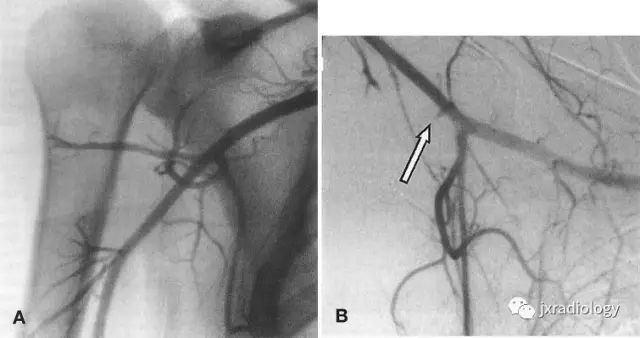

Before the advent of MR conventional angiography was the primary diagnostic modality. Angiography would show occlusion or compression of the posterior circumflex artery in the QS region.

在MR出现之前,常规血管造影是主要的诊断方式。血管造影将显示QS区域的后旋肱后动脉闭塞或压迫。

An angiogram of a patient with quadrilateral space syndrome. A, Digital subtraction angiogram with arm in adduction reveals patent posterior humeral circumflex artery. B, Angiogram of same patient with the arm in abduction reveals complete occlusion of the posterior humeral circumflex artery (arrow), confirming the diagnosis.同一病人上臂内收(A)与外展(B)时造影,B图箭头示旋肱后动脉完全闭塞。